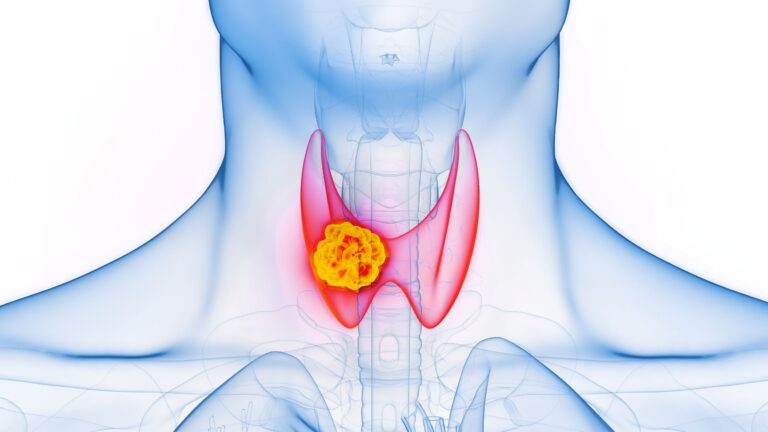

Rak pęcherzykowy tarczycy to jeden z typów nowotworów tarczycy, który rozwija się zwykle powoli i przez długi czas może przebiegać bez wyraźnych objawów. Wczesne wykrycie choroby jest kluczowe dla skutecznego leczenia i dobrego rokowania.

Rak pęcherzykowy tarczycy (ICD-10 C73) rozwija się z komórek pęcherzykowych tarczycy, które odpowiadają za produkcję, magazynowanie i uwalnianie hormonów tarczycy. Jest to nowotwór złośliwy, ale najczęściej rośnie powoli i przez długi czas nie daje wyraźnych objawów. Wykrycie go we wczesnym stadium zwiększa szanse na skuteczne leczenie i ograniczenie ryzyka przerzutów.

Tak, rak pęcherzykowy tarczycy jest uznawany za nowotwór złośliwy. W większości przypadków jego rozwój jest powolny, a przerzuty do odległych narządów występują rzadziej niż w przypadku bardziej agresywnych typów raka tarczycy, np. raka anaplastycznego. Mimo to wczesna diagnostyka jest kluczowa.